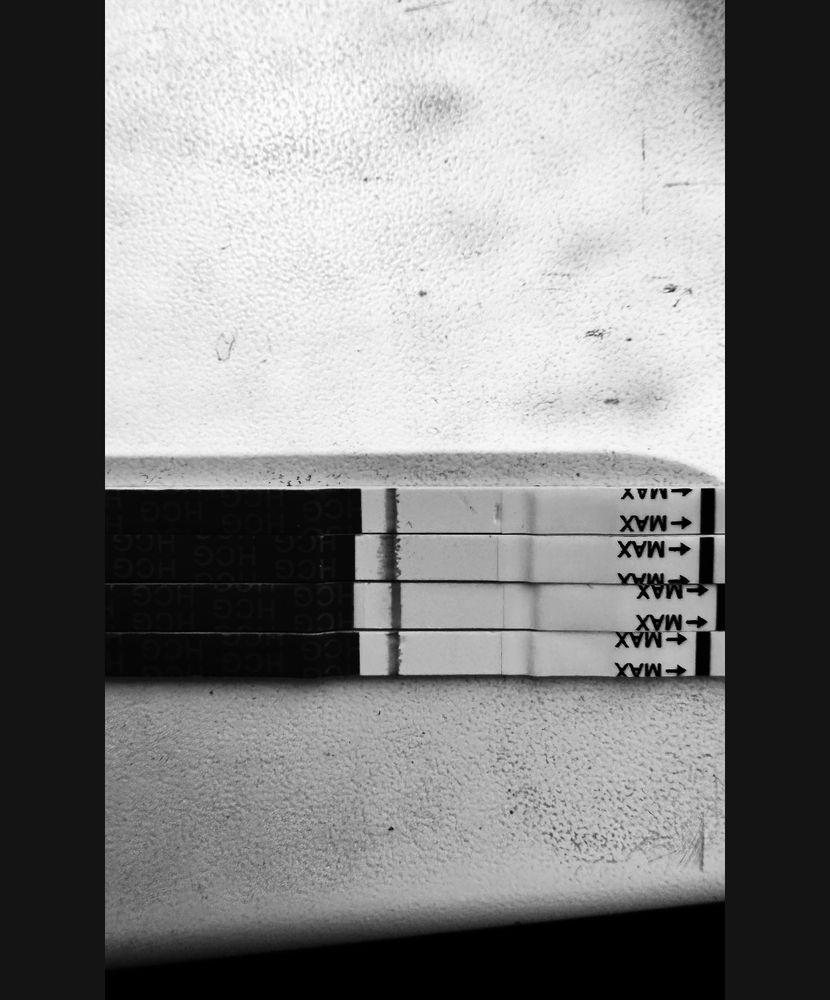

Девочки делала тесты начиная с 8 пдо , не знаю зачем 😂тапки не кидать ) последний тест 11пдо , я вижу тень , все тесты с одной пачки мама чек. Что думаете ?

Девочки делала тесты начиная с 8 пдо , не знаю зачем 😂тапки не кидать ) последний тест 11пдо , я вижу тень , все тесты с одной пачки мама чек. Что думаете ?

Тут явно место под полоску на всех. Для 10-11 ну это совсем слабо. Вечером повторите. Мои всегда вечером ярче. Мало ли, может и у вас так